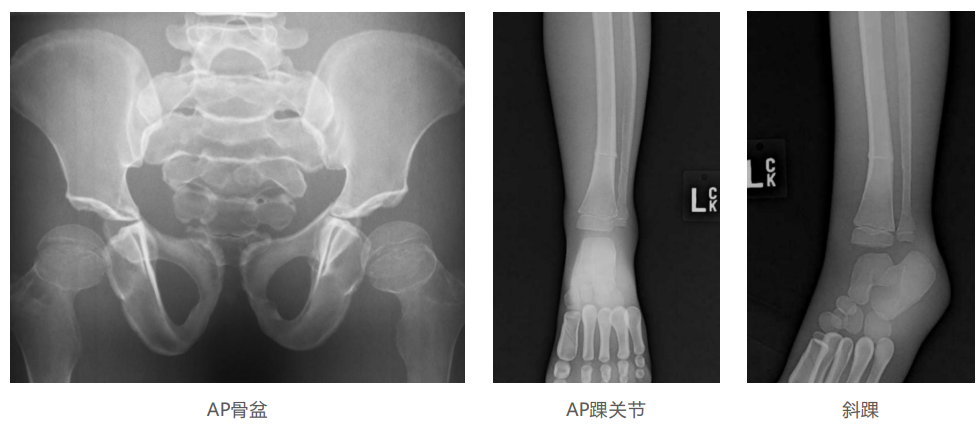

仿真人體模體旨在幫助教學(xué)和提高患者對(duì)體位、準(zhǔn)直和解剖學(xué)的理解,其廣泛的特點(diǎn)有助于安全、高質(zhì)量的人體影像學(xué)的有效指導(dǎo)。

模體的大小和結(jié)構(gòu)都代表了人體模體,使其便攜和易于定位。包括頭、胳膊和腿在內(nèi)的整個(gè)身體。該系列包括六個(gè)部分的模體可單獨(dú)或作為一個(gè)完整的集合。

右肢有伸直或彎曲兩種配置。左臂和左腿可選伴有或不伴有內(nèi)嵌骨折。

骨折版本包含最常見(jiàn)的人體骨折類型 ,包括脛骨扣帶骨折和腓骨普通骨折;

第一跖骨骨折;橈骨切開復(fù)位骨折 ,第二中間趾骨常見(jiàn)骨折。組件由適當(dāng)?shù)木郯滨ズ铜h(huán)氧材料制成,模擬人體組織的X射線衰減特性,用于診斷和治療能量范圍(50 keV - 25 MeV) 。 材料經(jīng)久耐用 ,耐沖擊,適合連續(xù)搬運(yùn)。透明的軟組織有助于解剖標(biāo)志的視覺(jué)指示。